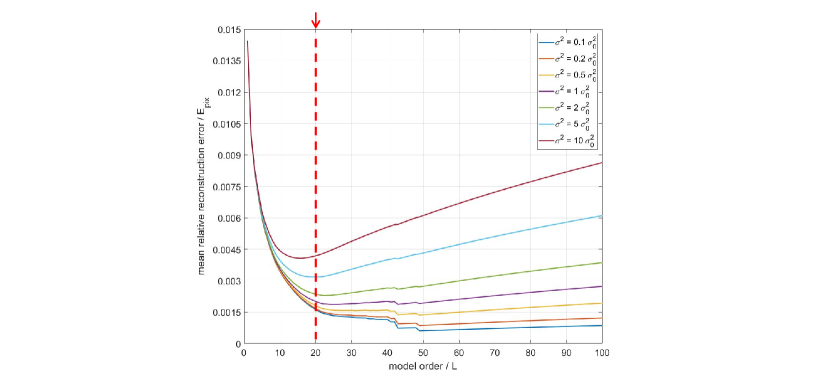

Using this equation, a simulation study is performed on the OCMR dataset[53], which is a public dataset containing multi-coil k-space data of cardiac MRI. The noise level is approximated by the intensity variance calculated from the empty region in the images. The reconstruction error is calculated for different values () for each data case. The mean is plotted to , which produces the error curve. Besides, is also changed to obtain the error curves under different noise levels. Seven noise levels () are simulated in this study. The best selected from this study is used in the following experiments.

The curves obtained from the simulation study are shown in Figure 3. It can be observed that when the model order increases, the reconstruction error curve will decrease first, and then will increase when reaches certain turning point. Obviously, the turning point is exactly the best model order in theory.

However, the position of the turning point is different for different noise levels. For low noise levels, the turning point is larger, which means greater is more preferable for reconstruction. For high noise levels, the turning point is smaller, which means smaller is better for reconstruction. In practice, the noise variance varies with the MRI hardware and environment conditions. As is shown Figure 3, a good balance between model performance and noise amplification is achieved at for a wide range of noise levels. Therefore, is selected as the model order in this work, which is used for all the PS model algorithms in this work.